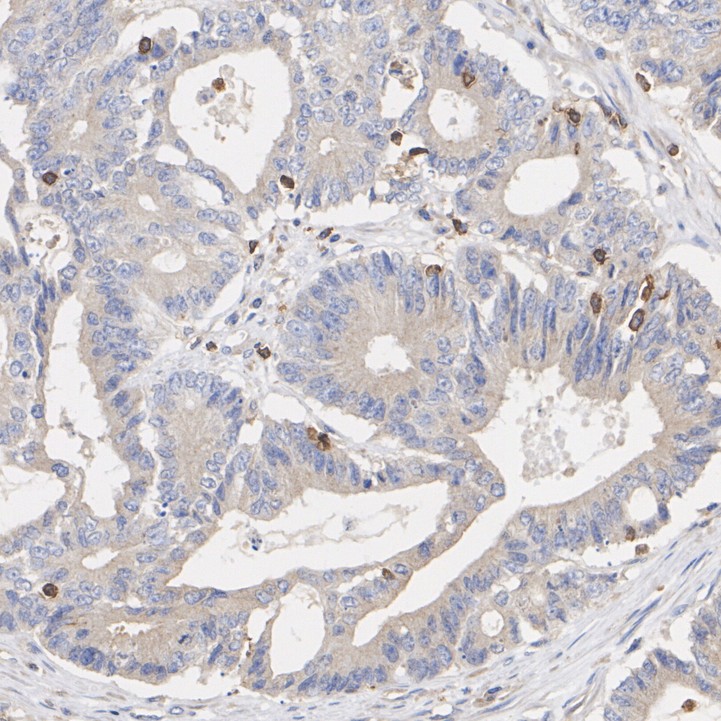

Immunohistochemical analysis of paraffin-embedded human colon cancer tissue with Rabbit anti-Phospho-GSK3 alpha (S21) antibody (HA723069) at 1/200 dilution.

The section was pre-treated using heat mediated antigen retrieval with Tris-EDTA buffer (pH 9.0) for 20 minutes. The tissues were blocked in 1% BSA for 20 minutes at room temperature, washed with ddH2O and PBS, and then probed with the primary antibody (HA723069) at 1/200 dilution for 1 hour at room temperature. The detection was performed using an HRP conjugated compact polymer system. DAB was used as the chromogen. Tissues were counterstained with hematoxylin and mounted with DPX.